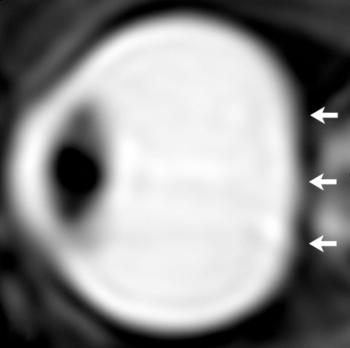

The results showed that, compared to short-duration astronauts, long-duration astronauts had significantly increased post-flight flattening of their eyeballs and increased optic nerve protrusion. Long-duration astronauts also had significantly greater post-flight increases in orbital CSF volume, or the CSF around the optic nerves within the bony cavity of the skull that holds the eye, and ventricular CSF volume—volume in the cavities of the brain where CSF is produced. The large post-spaceflight ocular changes observed in ISS crew members were associated with greater increases in intraorbital and intracranial CSF volume.

"If the ocular structural deformations are not identified early, astronauts could suffer irreversible damage," he noted. "As the eye globe becomes more flattened, the astronauts become hyperopic, or far-sighted."